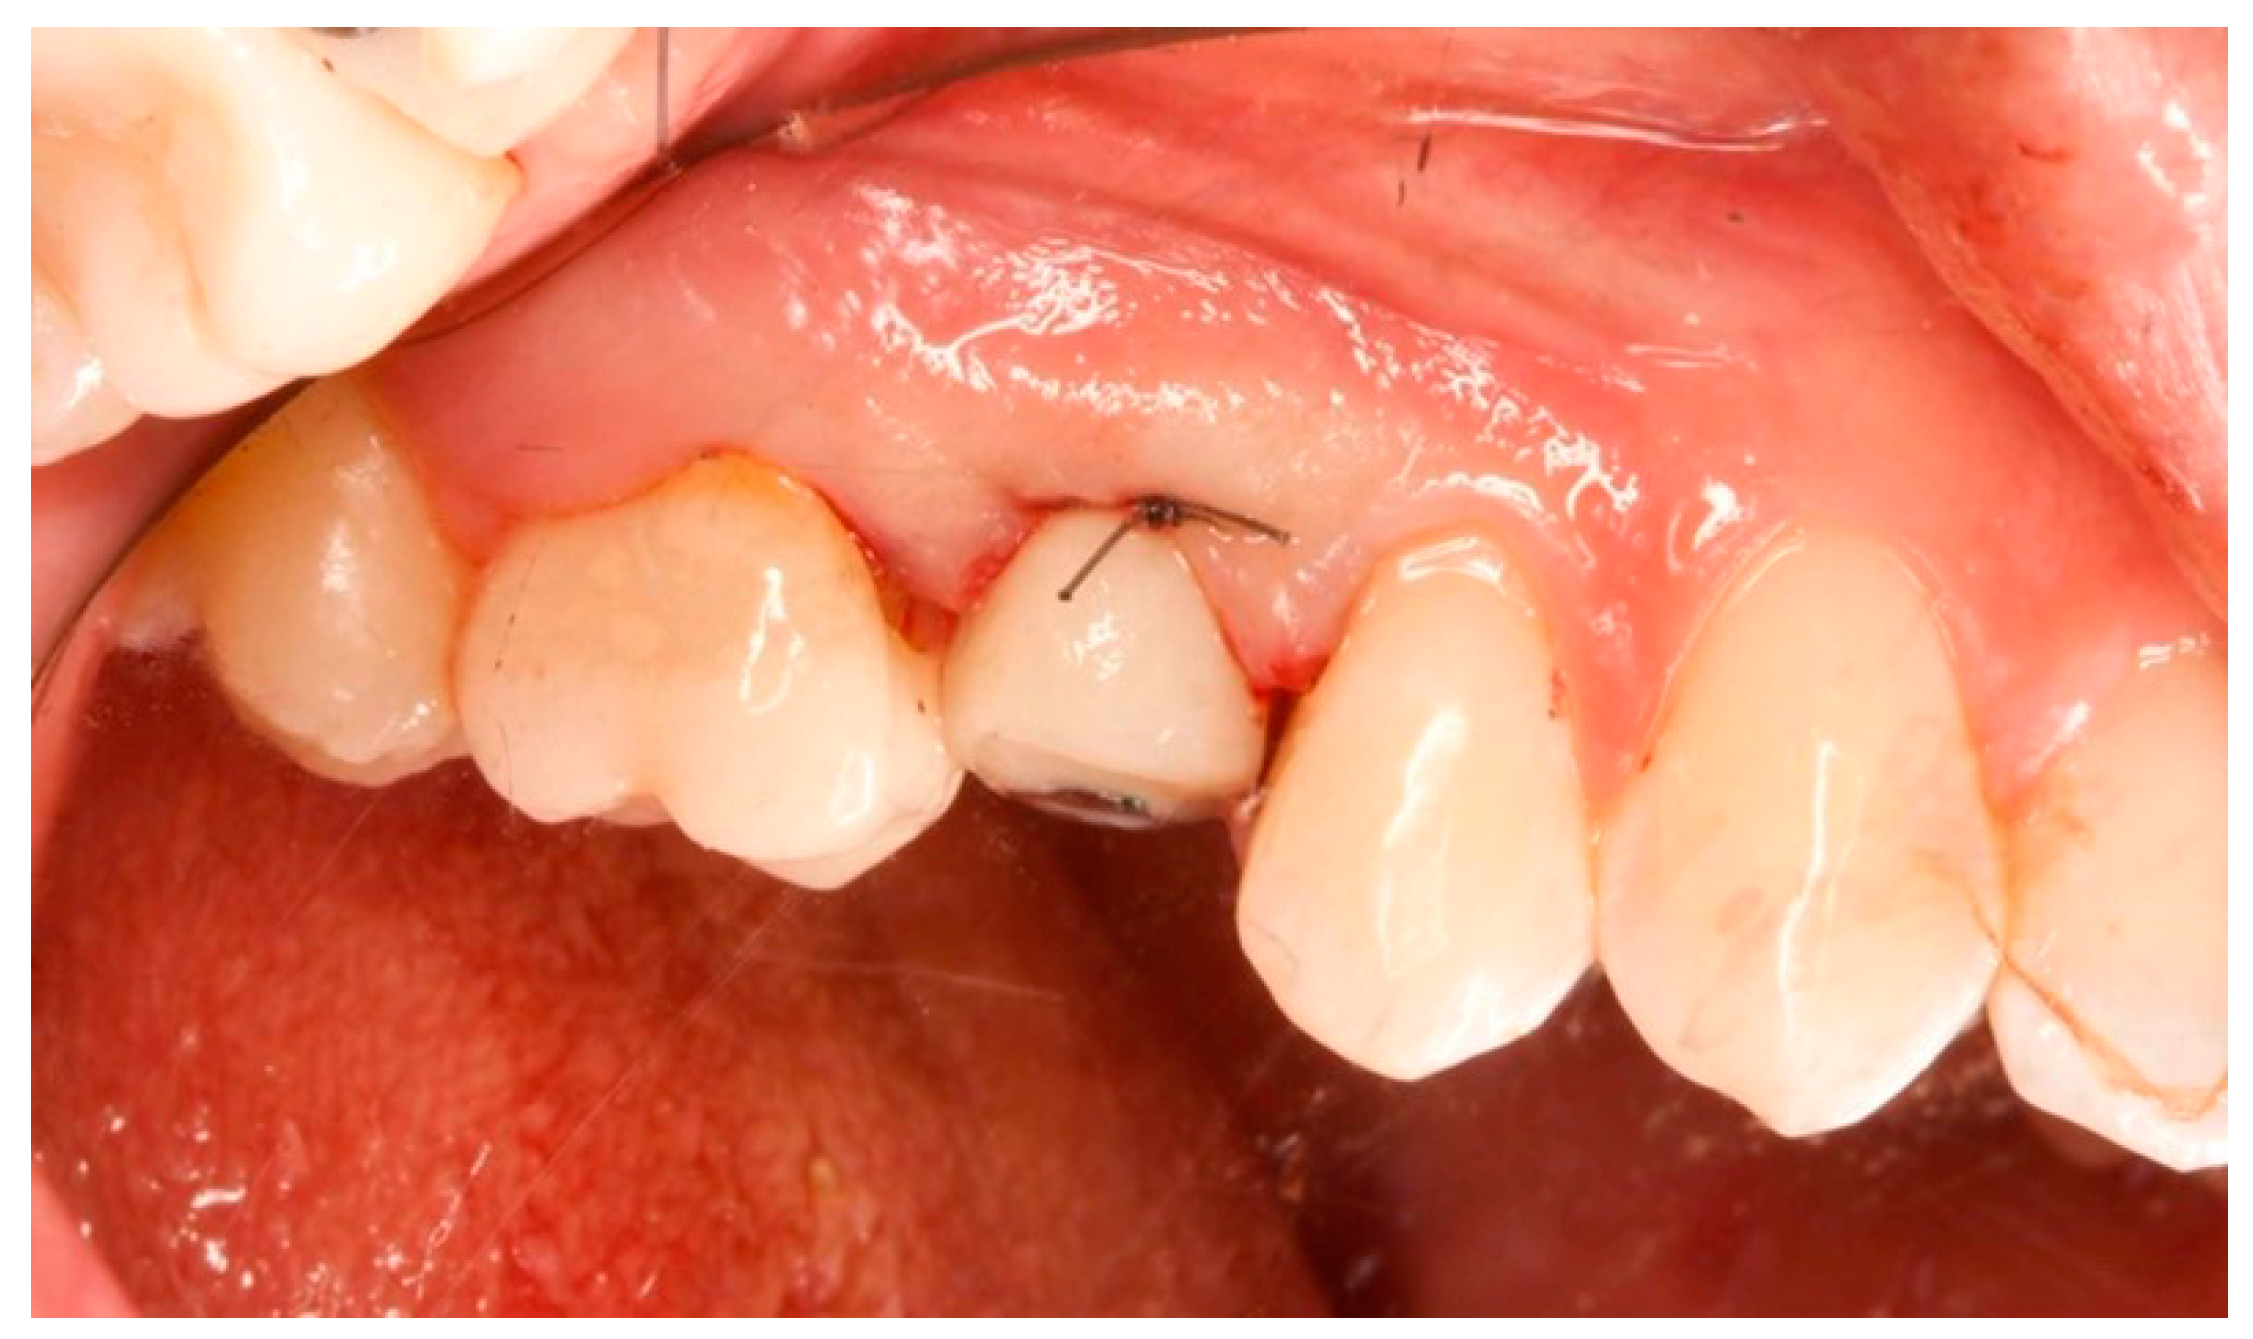

Figure 1.

Vestibular view prior to implant insertion of tooth 1.5.